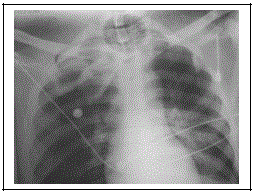

Podemos observar nesta radiografia de tórax a seguinte alteração:

Provas